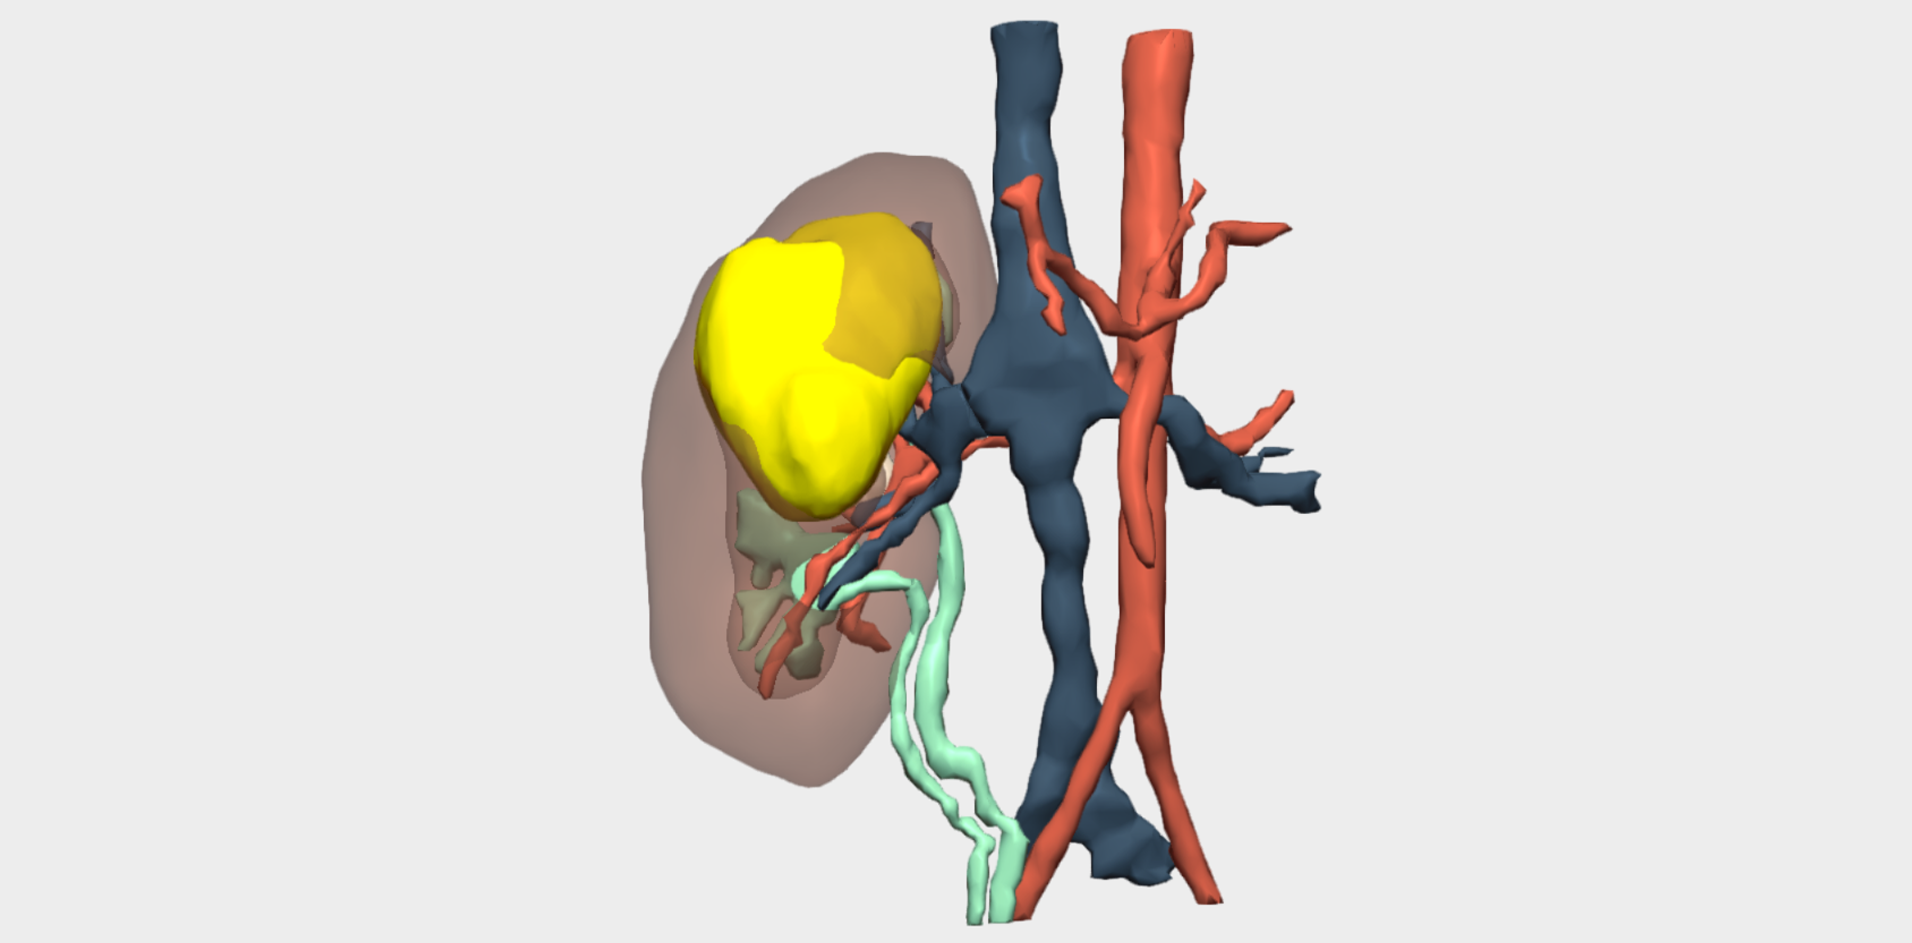

Following multidisciplinary assessment by the Oncology Committee, a right upper pole laparoscopic heminephrectomy was indicated for diagnostic histopathological analysis. Imaging studies were inconclusive and did not allow definitive diagnosis or exclusion of malignancy. Additional imaging performed at the Complejo Hospitalario Universitario de Albacete, including MRI and angio-CT, anticipated significant challenges in vascular localisation and dissection. The renal artery and vein bifurcated within the kidney, beneath the tumour and in close contact with it. Furthermore, the small calibre of these vessels limited precise visualisation of their anatomical course.

Three-dimensional reconstruction enabled precise localisation of the vascular bifurcation, revealing the presence of two arteries and two veins supplying each renal moiety —an anatomically relevant finding that had not been previously identified and was critical for surgical planning.

Detailed 3D anatomical analysis, combined with advanced functionalities such as arterial territory assessment and the ability to work intraoperatively with dual visualisation —3D reconstruction and laparoscopy displayed simultaneously— was a key factor in the success of the procedure.